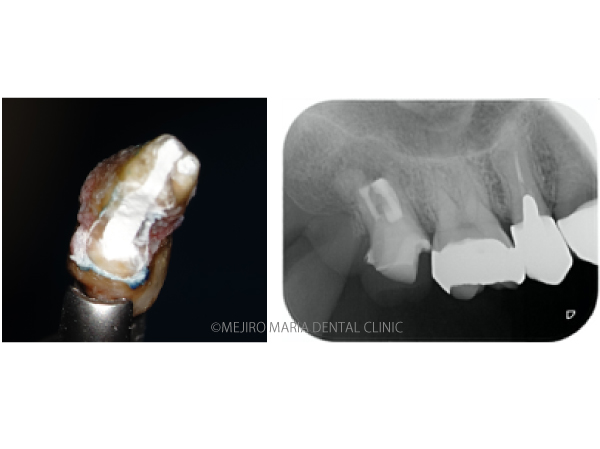

• 目白マリア歯科_意図的再植術0625メイン

【症例】意図的再植術|歯根破折歯を保存したチャレンジケース